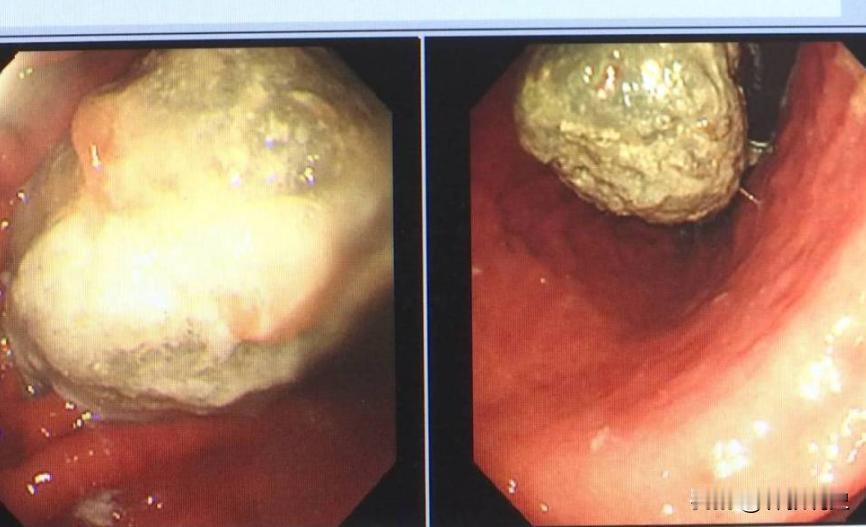

“悲剧还是发生了!”12月12日报道,江苏常州一女子吃完饭后,又吃了十多颗山楂,结果几个小时后,她感觉胃像被针扎了一样疼!不料此后几天里,女子总是吃什么吐什么,去医院检查,发现胃里面竟有一颗10厘米的结石。[思考] 晚饭后连吃十几颗新鲜山楂,常州一位贾女士当晚就感到胃部针扎般疼痛,随后几天更是腹胀、呕吐,无法进食。 就医后才发现,胃里竟长出一个直径达10厘米的结石,这类病例在秋冬季节并不少见,医生们近期已接诊多位因食用山楂或柿子形成胃结石的患者。 许多人疑惑,山楂不是助消化吗,怎么反而会长结石?关键在于其中的鞣酸。 尤其是在空腹状态下,鞣酸在胃酸作用下会与蛋白质结合形成沉淀物,再混合果胶、纤维素,像滚雪球一样越滚越大,最终形成坚硬的结石,除了山楂,未成熟的柿子、黑枣也是高鞣酸食物。 哪些人更容易中招呢?消化功能本身较弱的老人和儿童首当其冲,减肥人士空腹时间长胃酸浓度高,糖尿病患者胃动力不足,也都是高风险人群,需要格外注意。 想要安心享受山楂的美味,记住几个关键点,千万别空腹吃,最好饭后1-2小时再食用。每天食用量最好控制在10颗以内,儿童和老人更要减量。 避免与高蛋白食物如海鲜、牛奶同食,以防鞣酸与蛋白质反应,如果食用后出现持续胃痛、腹胀,不要自行服药,应及时就医检查。 针对此事件网友评论: “我的天!我昨天刚吃完一串糖葫芦,看到这个新闻感觉胃里已经开始不对劲了……以后可真得管住嘴了。” “十厘米的石头?这也太吓人了!我一直以为山楂是助消化的,家里老人小孩都常吃,看来好东西也不能过量啊。” “科普一下:主要是山楂里那个叫‘鞣酸’的东西,碰上胃酸和蛋白质,就容易结成块。所以别空腹吃,也别跟海鲜、牛奶这些高蛋白的一起吃。” “我们这有个偏方,说胃里结了石头喝可乐能化掉,不知道真的假的?有没有懂的出来说说?” “楼上别乱试!新闻里说了,喝可乐得在医生指导下进行,自己乱喝万一结石把胃磨出溃疡,再喝可乐可能胃穿孔,更危险!” “这让我想起去年也是这时候,我家孩子爷爷因为吃了几个柿子进了医院,原理跟这个差不多。家里有老人和肠胃不好的,一定要多提醒!” “看来冬天这几样热门零食——山楂、柿子、黑枣,个个都是‘深藏不露’的高手,美食虽好,健康第一!” “吓得我赶紧放下了手里的山楂片……不过说实话,现在有些山楂制品为了口感加了好多糖,可能比鲜山楂的隐患还多。” 这个冬天,你或者你身边的人有没有因为贪嘴某样应季美食而遇到类似的健康小插曲呢?欢迎在评论区分享你的经历或困惑,你的故事或许就能帮到其他人! 信息来源:常州网